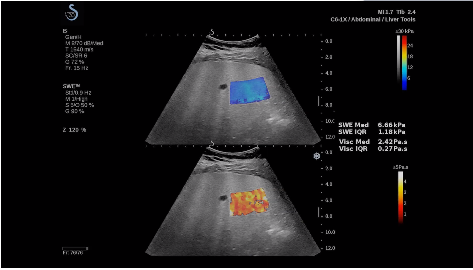

法國(guó)聲科影像(SuperSonic Imagine,SSI. Euroniex:FR0010526814)近日發(fā)表公告,宣布其研發(fā)的新一代“極速”超聲成像平臺(tái)(UltraFast Imaging),首次實(shí)現(xiàn)了肝臟的多項(xiàng)超聲定量評(píng)估新指標(biāo)同步檢測(cè),包括:Att PLUS,SSp PLUS和Vi PLUS等,基本涵蓋肝臟相關(guān)病理變化指征的如纖維化、脂肪變、炎癥等。據(jù)悉,此多項(xiàng)新技術(shù)新將搭載于新Aixplorer系列E超系統(tǒng)。

E超相關(guān)技術(shù)已被多項(xiàng)多中心大樣本研究證實(shí)對(duì)于肝纖維化無創(chuàng)評(píng)估有重要意義,同時(shí)也可全面應(yīng)用于乳腺、甲狀腺、肝臟、前列腺、肌骨、婦科等全身各組織器官的定量評(píng)估和鑒別診斷。在慢性肝臟方面,聲科E超的肝臟相關(guān)定量診斷技術(shù)集,于2018年獲得美國(guó)FDA認(rèn)證,成為FDA歷史上首次獲批的單病種超聲全面定量解決方案。

E超是在原有B超、彩超(彩色多普勒CDFI)基礎(chǔ)上研發(fā)成功的新一代超聲剪切波彈性成像系統(tǒng),是一種能夠全面應(yīng)用于表淺組織、腹部臟器,血管等方面的組織彈性成像技術(shù)。根據(jù)組織硬度彈性值的不同,有效鑒別實(shí)性腫瘤的良惡性。對(duì)于惡性病變的診斷具有較高的特異性和敏感性,尤其對(duì)于甲狀腺、乳腺、前列腺等小器官,能夠完成常規(guī)超聲不能完成的組織定量分析,可以實(shí)時(shí)、全幅、全定量獲得組織彈性(硬度)信息,為鑒別腫瘤的良惡性提供客觀、量化的診斷依據(jù)。